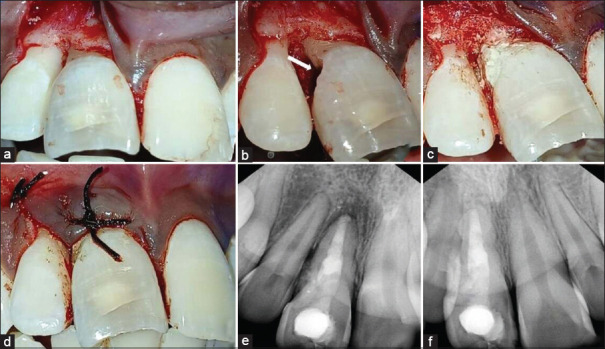

The presence of both a pathologic external cervical resorption (ECR) and an iatrogenic over-enlarged root canal with a widened apex can significantly compromise the structural integrity of a tooth. Furthermore, regular restorative-endodontic management of the involved tooth poses many procedural challenges and difficulties. However, a multi-modal approach involving nonsurgical and surgical procedures with the application of advances in endodontics can help to manage and salvage such a tooth. This article aims to report on a case of multi-modal management with the application of cone-beam computed tomography, micro-endodontics, bioactive and biomimetic materials, and monobloc effect to manage and structurally rehabilitate and reinforce a tooth affected by both ECR and over enlarged canal with a widened apex. This multi-modal approach was applied with nonsurgical and surgical treatments to restoratively and endodontically manage the affected tooth. Clinical and radiographic follow-up of the tooth was uneventful and showed satisfactory and favorable outcomes.